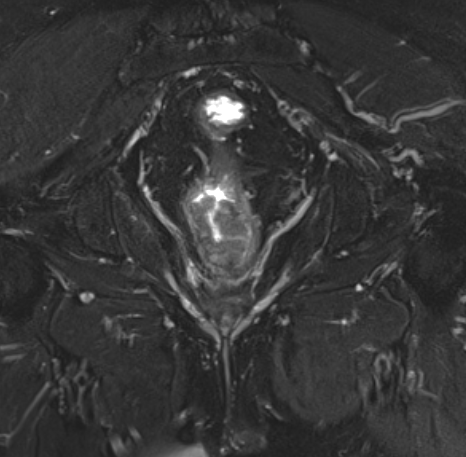

Магнитно-резонансная томография органов малого таза (прямой кишки)

Магнитно-резонансная томография не является методом выбора для первичной диагностики рака прямой кишки, но в ряде случаев является незаменимым помощником лечащему врачу. Оценка распространенности опухолевого процесса, выбор тактики лечения онкологического пациента, принятие решения о целесообразности и объеме оперативного вмешательства - те ситуации, когда МРТ НЕОБХОДИМА. Кроме того метод показан для контроля и оценки результатов лечения: хирургического, лучевого, химиотерапии; а также для определения дальнейшей тактики ведения пациента.

Возможности МРТ в диагностике рака прямой кишки:

• Визуализация опухоли, определение ее верхней и нижней границ, а также степени вовлечения в процесс кишечной стенки;

• Определение степени бокового распространения опухоли относительно стенки кишки, мезоректума и собственной фасции;

• Определение отношения опухоли к структурам тазового дна и сфинктерному аппарату;

• Определение состояния мышц тазового дна;

• Выявление и оценка состояния лимфатических узлов и лимфооттока в области малого таза;

• Контроль результатов хирургического лечения, лучевой терапии и химиотерапии; динамика.

Исходя из вышесказанного, на современном этапе развития медицины, МРТ прямой кишки является "ЗОЛОТЫМ СТАНДАРТОМ" при обследовании и дальнейшем ведении пациентов с диагнозом опухолевого поражения прямой кишки.